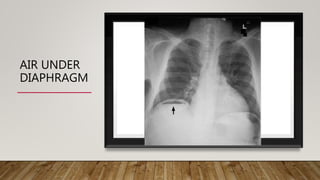

ERECT CHEST X-RAY

• Air under diaphragm

AIR UNDER

DIAPHRAGM

• Perforation of a hollow viscus – e.g. a duodenal ulcer – free air under

diaphragm in an upright X-ray film